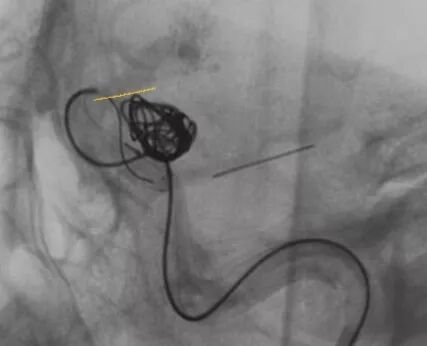

填了一个HydroFram8×30的弹簧圈成篮,从形态来看,应用双微导管技术栓塞是能够完成手术的

Enterprise4.5×22支架半释放,支架尾端的有效段能恰好覆盖全瘤颈

支架有效段完全释放,这个时候开始将支架导管往前顶,让导管头端尽量越过瘤颈远端

支架完全释放

释放后的造影。突入颈内动脉和后交通动脉内的弹簧圈被压入瘤体内